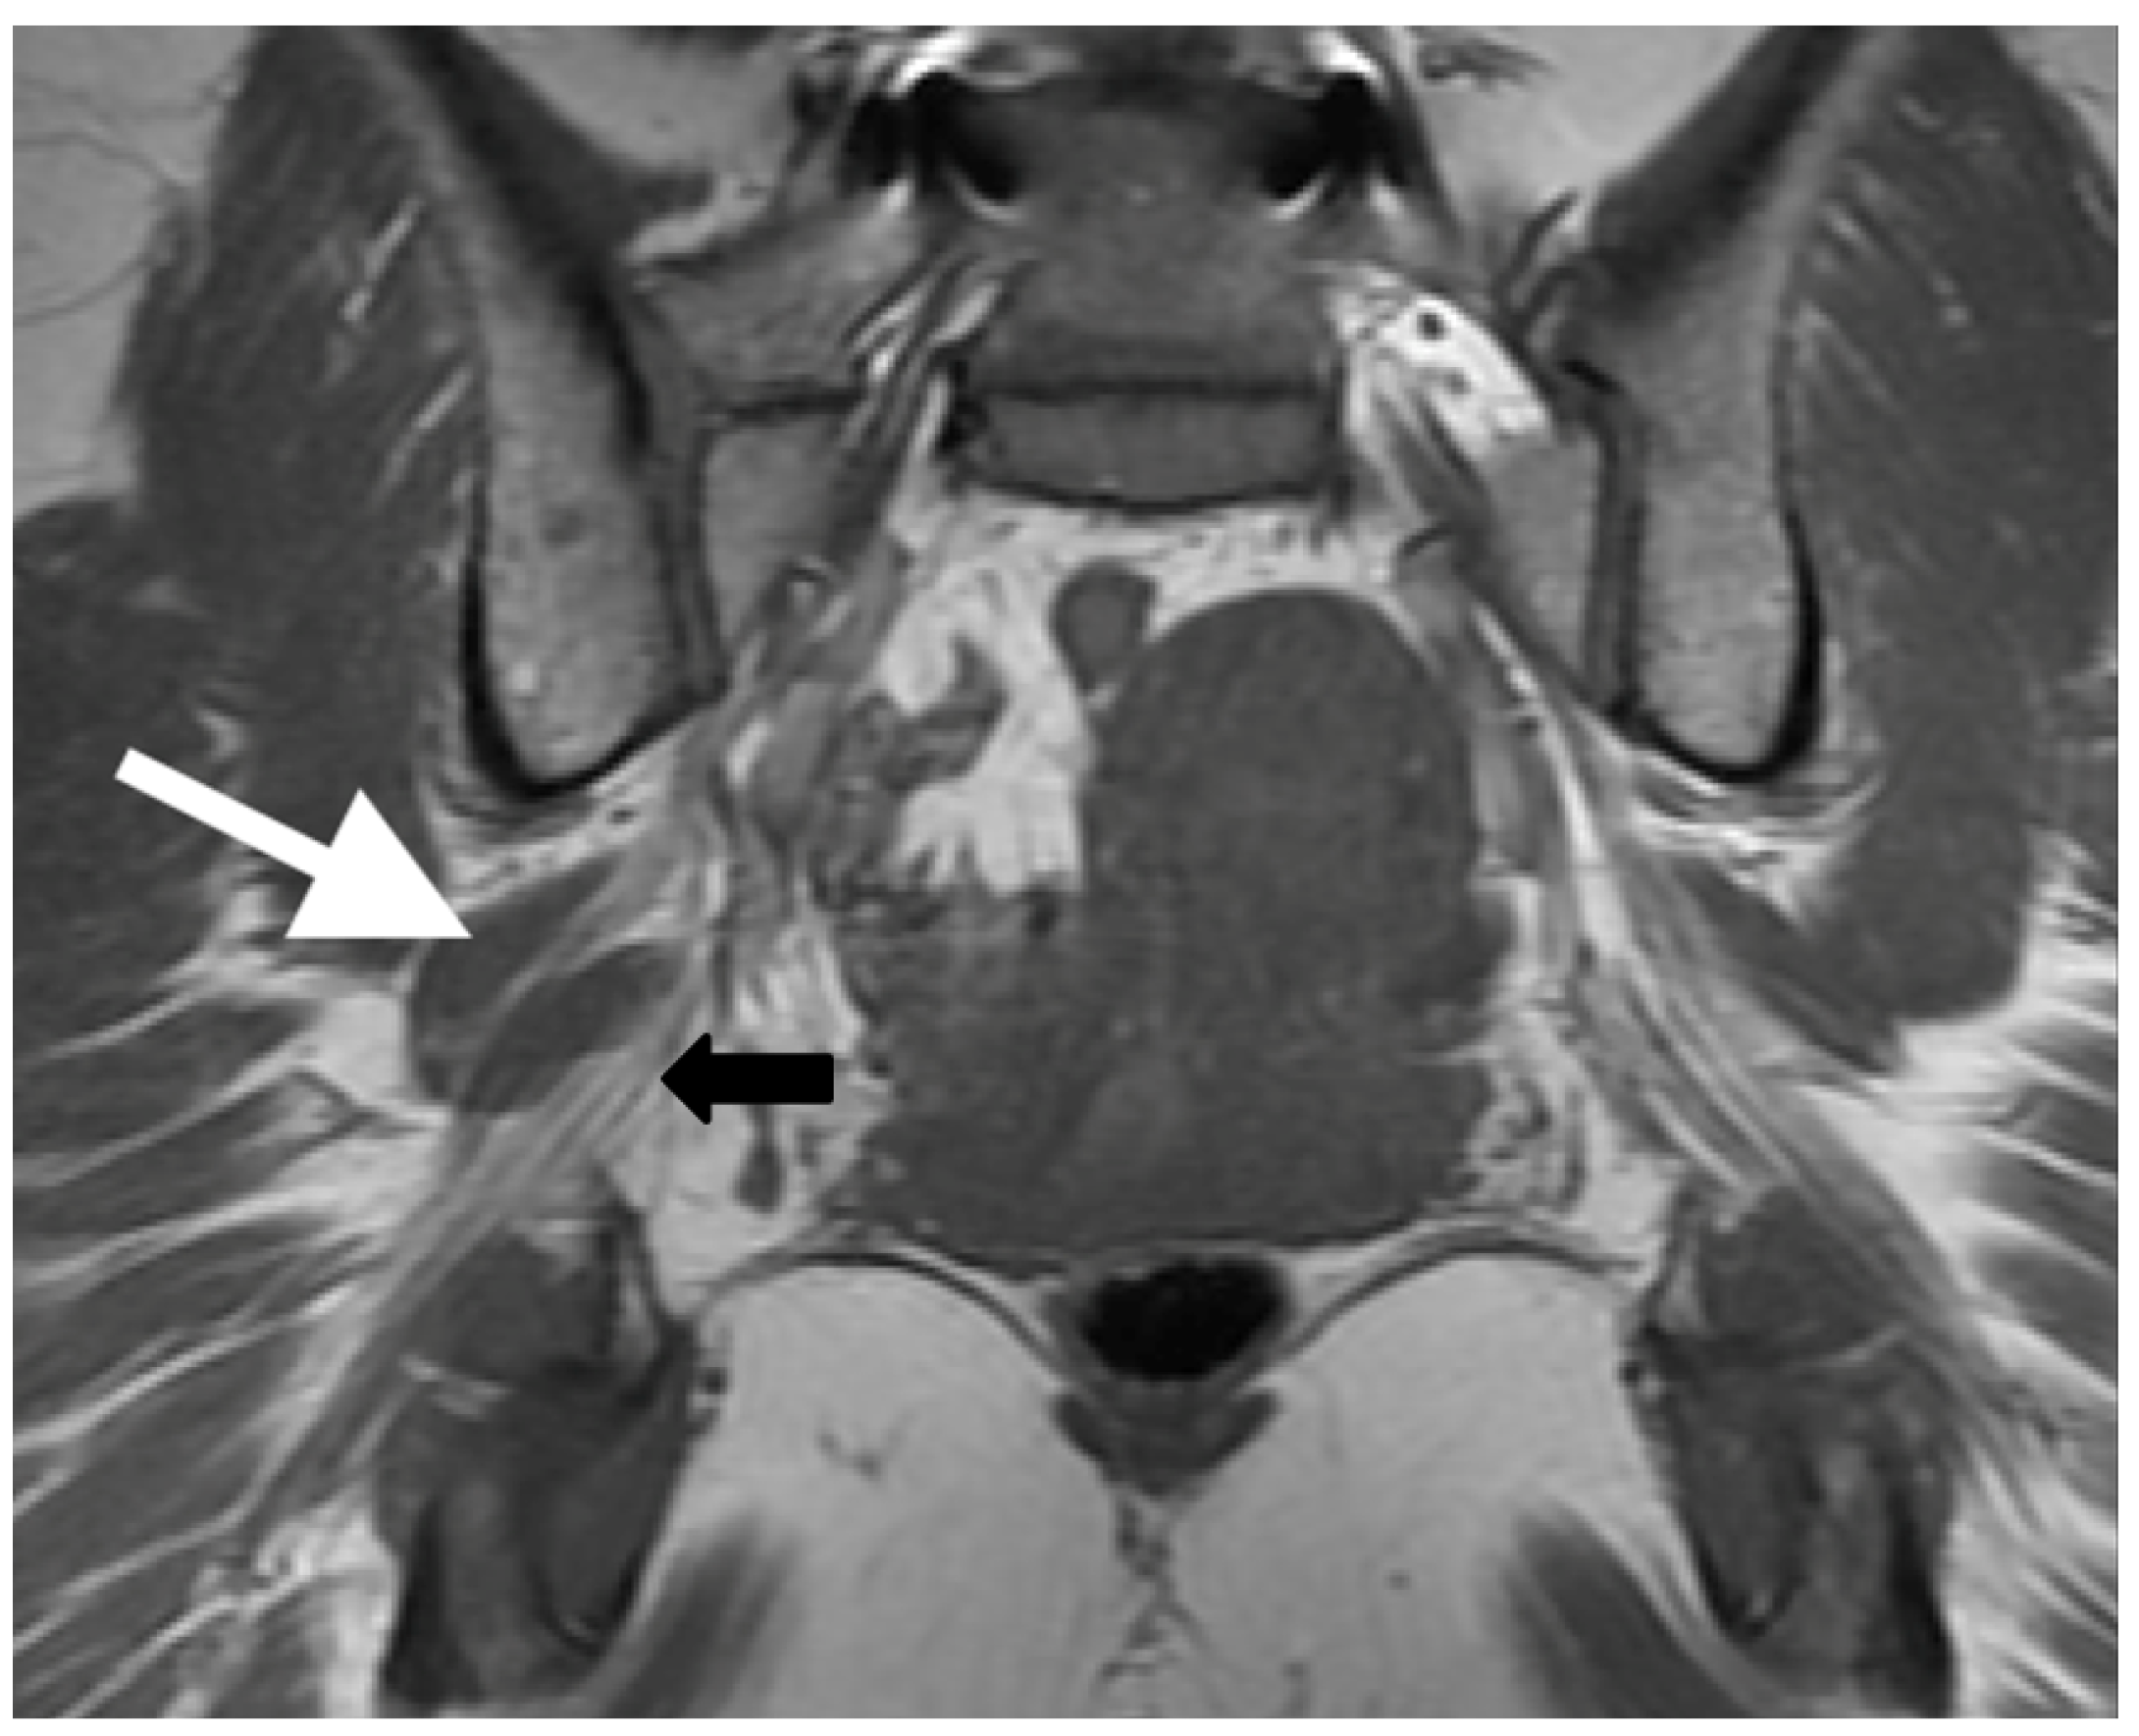

3.2. MR Neurography of the Sciatic Nerves

3.3. Sciatic Nerve Correlation with Findings at MR Neurography